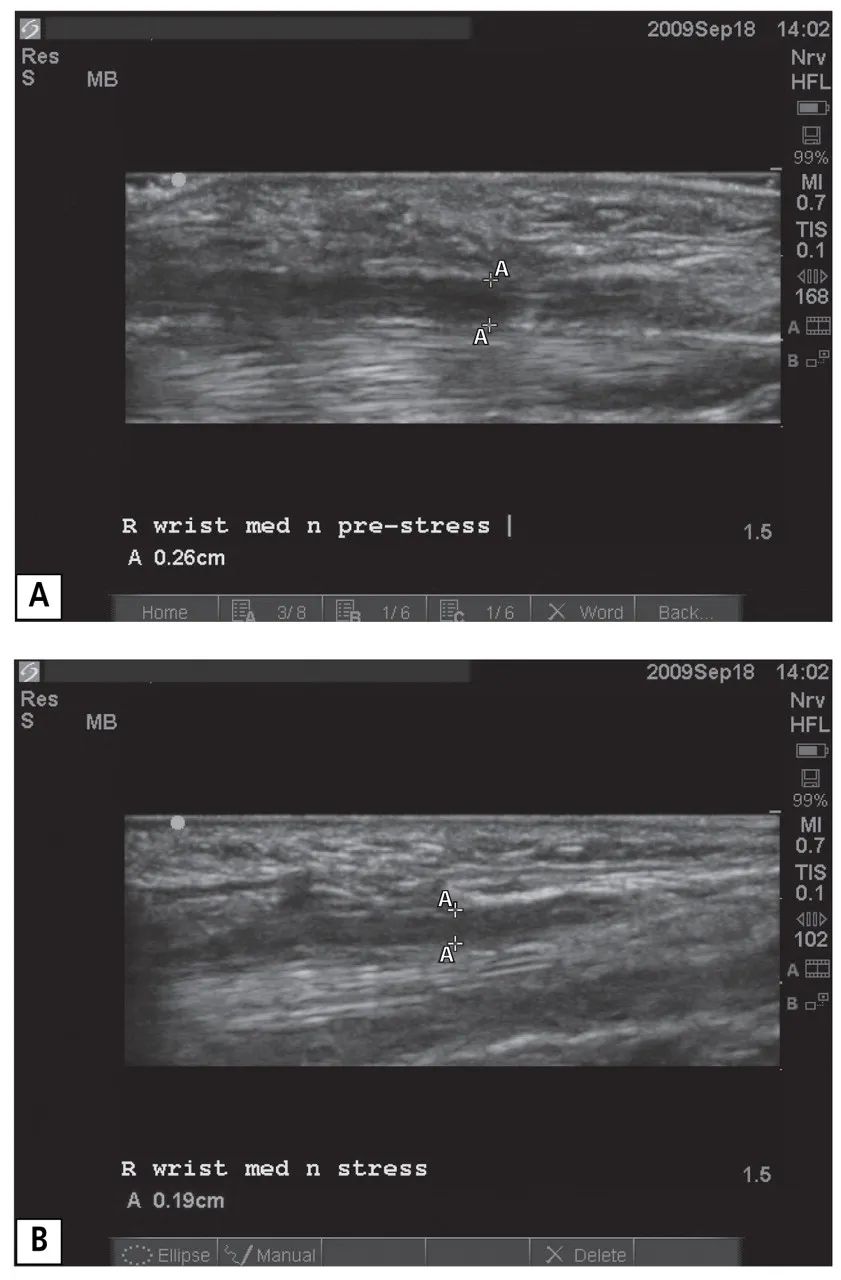

與病例1的病人一樣,病例2的病人在做完電診斷后也做了超聲造影。該成像顯示右正中神經(jīng)增大,橫截面測量值為16平方毫米,位于豌豆骨水平??v向成像(圖5)顯示在動態(tài)壓力測試期間,右正中神經(jīng)受壓——正中神經(jīng)直徑從預應力測量的0.26厘米降到應力測量時的0.19厘米,代表了幅度為27%的壓迫性變窄。

圖五

一位患有腕管綜合征的56歲女性的右手腕的超聲圖像(病例2)。正中神經(jīng)在預應力(A)和應力(B)期間的縱向圖像描述了 "A "標記之間的神經(jīng)直徑測量。測量結果顯示,最初的神經(jīng)直徑為0.26厘米,在壓力下下降到0.19厘米。沿著神經(jīng)的上表面(即腹側)可以看到輕微的壓痕或壓扁,魚際肌向下凸起(即背側)。